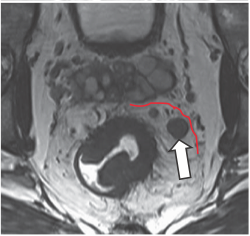

- T4: được chia T4a: khối u trực tiếp xâm lấn thanh mạc hoặc cân mạc treo trực tràng. T4b: khối u xâm lấn trực tiếp hoặc dính vào các tạng, cơ quan khác.

Hình 6. Sự giảm tín hiệu của khối u xâm lấn vào thành sau âm đạo